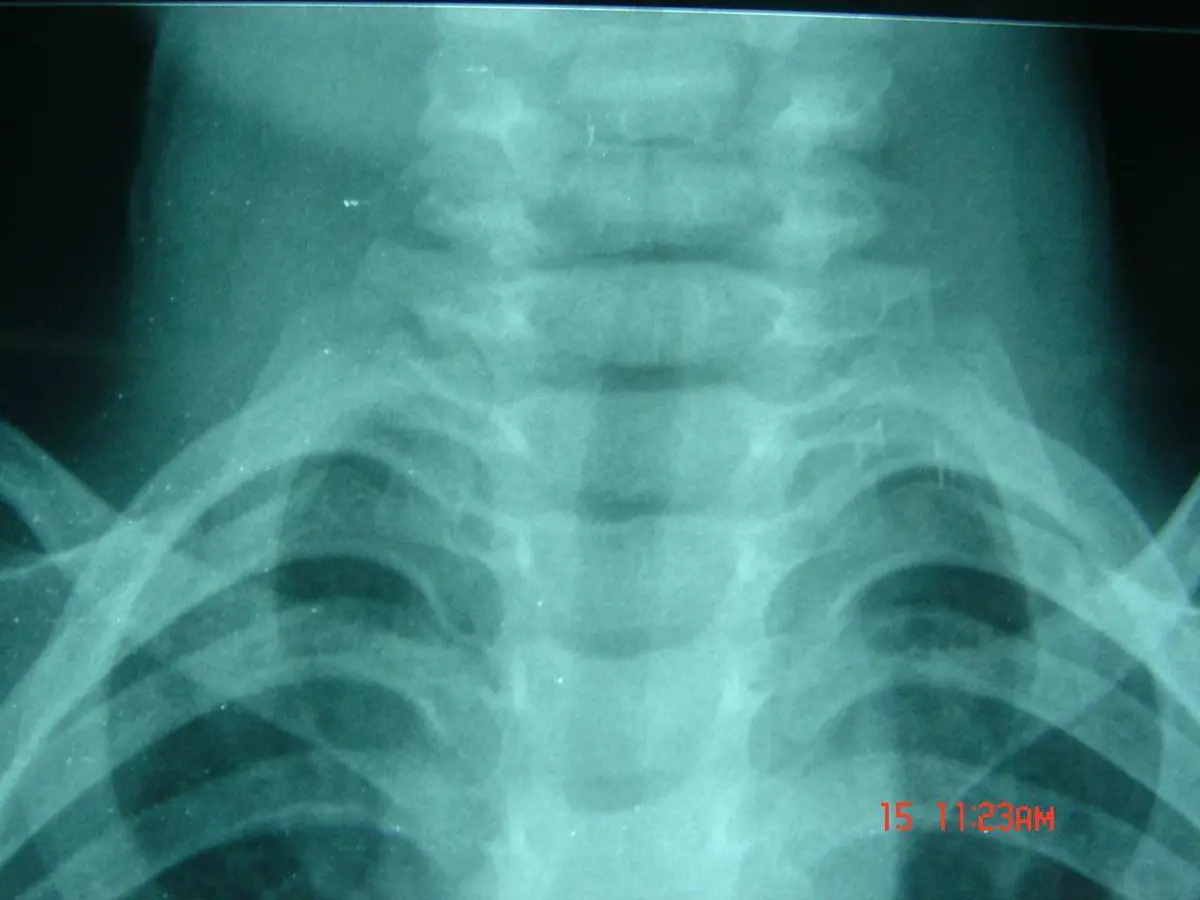

本題為小兒上呼吸道疾病的圖像診斷。一位 3 歲男童出現發燒、咳嗽、喉嚨痛與聲音沙啞,血液檢查以淋巴球增多為主(lymphocyte 50%),X 光影像呈現特徵性的「鐘樓徵(steeple sign)」,整體表現最符合哮吼(croup),又稱急性喉氣管支氣管炎(acute laryngotracheobronchitis)。

本題提供一張小兒頸胸部正面 X 光(AP view)。影像重點觀察:

- 聲門下區域(subglottic region):氣管在聲帶下方呈對稱性「鉛筆狀」逐漸收窄,形成倒 V 形,狀似教堂鐘樓,即著名的「鐘樓徵(steeple sign)」。正常小兒的聲門下氣管應有一定寬度,而本影像可見明顯的對稱性收窄。

- 肺野:兩側肺野清晰,無實質化(consolidation)或浸潤(infiltration),排除肺炎的可能。

- 縱膈與心臟輪廓:正常,無擴大或偏移。

臨床意義:steeple sign 是病毒性哮吼的特徵性 X 光表現,係因副流行性感冒病毒(parainfluenza virus)引起的聲門下黏膜水腫造成。需注意 steeple sign 的敏感性約 50%,並非所有哮吼病例都會出現,且其他上呼吸道感染偶爾也可出現相似表現;因此診斷仍以臨床表現為主,影像為輔。